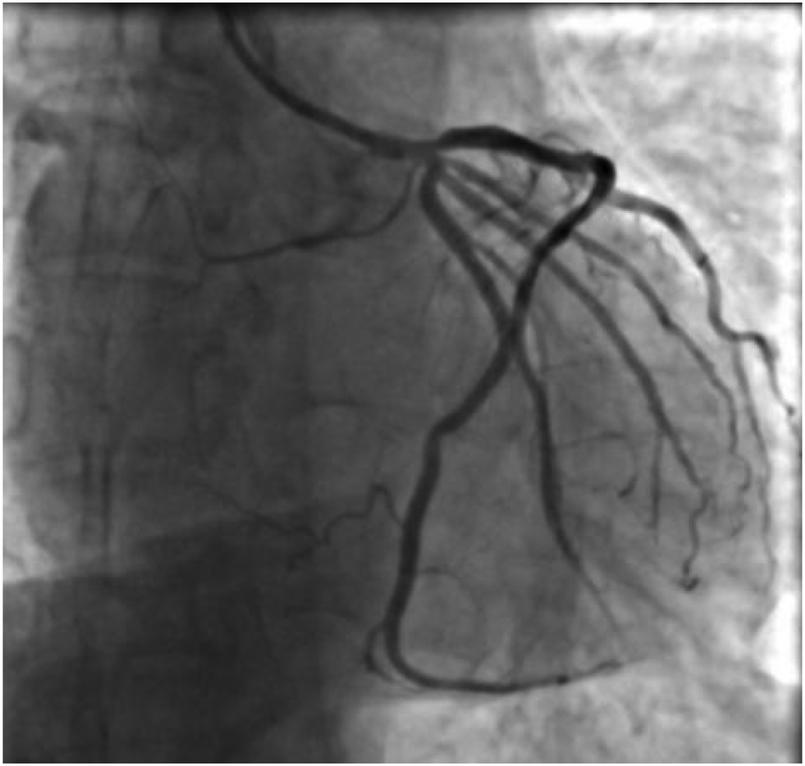

A 59-year-old male was admitted to our center, complaining of persistent chest pain over three days. He reported a 40-year history of heavy smoking and sporadic alcohol consumption for 18 years. His medical, allergy, and family histories were unremarkable. On admission, myocardial injury biomarkers revealed a myoglobin level of 45.4 ng/ml (0–121 ng/ml), a CK-MB mass of 4.85 ng/ml (0–3.38 ng/ml), and an ultrasensitive troponin I level of 2.47 ng/ml (0–0.034 ng/ml). The electrocardiogram (MAC800 model, GE Company) revealed an acute, extensive anterior wall myocardial infarction (Figure 1). Further, an echocardiogram (vividE9 model, GE Company) identified a left ventricular ejection fraction amounting to 56%, coupled with segmental motion abnormalities of the ventricular wall and a decreased amplitude of the lower ventricular septal pulsation. Following the diagnosis of “coronary artery atherosclerotic heart disease, extensive anterior myocardial infarction with Killip grade I classification”, a coronary angiogram was executed on the fifth day of the patient's hospital stay. Local stenosis of 95% within the proximal Left Anterior Descending artery (LAD) was evident, with a Thrombolysis in Myocardial Infarction (TIMI) flow grade of 3 (Figure 2A). Meanwhile, the Left Circumflex artery (LCX) showed non-significant stenosis, maintaining a TIMI grade of 3 (Figure 2B). Moreover, diffuse stenosis from the proximal to middle and distal segments of the Right Coronary Artery (RCA) was noted, along with greater than 90% stenosis, preserving a TIMI grade 3 flow (Figure 2C). We proposed to perform stenting for LAD, but the patient had a sudden onset of a peripheral red rash, decreased intracoronary pressure, and dyspnea during angiography. Re-evaluation angiography revealed proximal LAD occlusion, stenosis of the Obtuse Marginal artery (OM) and LCX, and diffuse RCA stenosis with distal segment occlusion (Figure 3A). The patient's blood pressure dropped to 55/35 mmHg, while his heart rate was 108 bpm. We attributed this to an allergic reaction and promptly administered adrenaline 0.1 mg, dexamethasone 10 mg, morphine injection 3 mg immediately, and norepinephrine infused to relieve the allergic reaction and maintain blood pressure. At the same time, continuous and large amounts of intracoronary nitroglycerin was given, after which the patient's symptoms gradually subsided, stenosis improved (Figure 3B), and RCA stenosis improved significantly after half a minute of nitroglycerin administration (Figure 3C). Following a mid-segment LAD stent implantation, blood flow was restored (Figure 4). Postoperatively, his heart rate was 103 bpm, his blood pressure was 107/63 mmHg, and he was transferred to the coronary care unit for further surveillance. Postoperative examination: the patient was clear and cooperative,but a generalized red rash remained. He was diagnosed with Type II Kounis Syndrome with cardiogenic shock induced by iodophorol. His management included promethazine, vitamin C, norepinephrine and dopamine, after which the patient's blood pressure was maintained at 100/60 mmHg. On the first postoperative day, his blood pressure was 106/63 mmHg, his pulse was 75 bpm, and his level of consciousness was normal. The red rash gradually faded. Laboratory studies exhibited a cardiac troponin I level of 0.582 ng/ml (0–0.034 ng/ml) and an elevated high-sensitivity C-reactive protein level of 87.52 mg/L (0–3.5 mg/L). His IgM level was normal at 0.55 g/L (0.3–2.2 g/L), and his IgE level was less than 18.80 IU/ml (<100 IU/ml). Four days after the surgical intervention, the patient reported no discomfort, and his ultrasensitive troponin I level was down to 0.159 ng/ml (0–0.034 ng/ml). He was discharged with instructions for regular antiplatelet medication and future caution with contrast agents.

Figure 4

Coronary angiogram showing no residual stenosis after placement of 1 stent in the proximal segment of the LAD with anterograde flow TIMI grade 3.